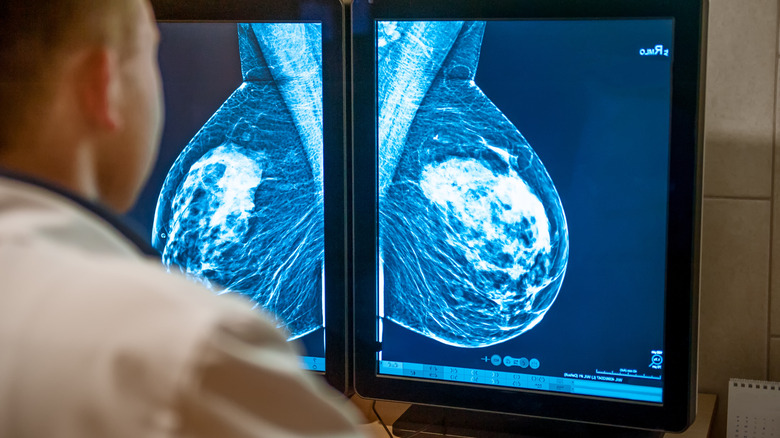

Currently, mammography screenings are the best way to identify breast cancer in its early stages. A mammogram, which is a low-dose X-ray picture of the breast tissue, allows medical professionals the ability to find instances of cancer up to three years before it presents physical symptoms. According to BC Cancer, identifying breast cancer early is imperative to help women receive access to a broader range of treatment options and increase their chance of recovery. Furthermore, regular screenings are proven to reduce breast cancer deaths by more than 25%.

Now that you know how to prepare for a mammogram let's talk about what the procedure actually entails. According to RadiologyInfo.org, a mammogram is an outpatient procedure that uses a small dose of ionizing radiation to produce pictures of the insides of the breasts. The mammography equipment looks like a large box with a tube, which is what produces the x-ray images. It features a platform to rest the breast on and a plastic paddle that compresses the breast.

During the procedure, you stand in front of the unit with your breast on the platform (via CDC). The mammogram unit compresses the breast to even out the breast thickness and help make the tissue more visible. It also thins the breast, which allows for a lower dose of radiation to get an accurate image, and minimizes movement that can alter the image quality. You may be asked to hold your breath to help reduce movement as the pictures are taken. The X-ray technician will likely place stickers on prominent scars, birthmarks, and nipples to avoid confusion for the radiologist looking at the images later.

During a mammogram, you may be asked to move around to obtain the images the mammographer needs. A mammographer typically takes a top-to-bottom view and a side-angled view. Overall, most mammograms take between 20 to 30 minutes to complete. It is generally described as an uncomfortable procedure, although it only takes a few moments on each side.

There are several different types of mammograms, and it is important to know which you are getting before your first appointment. According to BreastCancer.org, there are two main types: 2D digital mammograms and 3D mammograms, which are also referred to as digital tomosynthesis. The technique for each procedure is the same. However, the types of images they produce are drastically different.

A 2D digital mammogram creates a 2D image of the breast. This is the most common form of digital mammography and includes the standard top and side angle images (via Fox Chase Cancer Center). 3D mammograms on the other hand take multiple images of each breast. These images are then compiled in a computer to paint a complete picture of the breast.

Currently, not all hospitals have access to a 3D mammography unit. However, this cutting-edge screening technology not only helps reduce the rate of false positives and repeat imaging procedures but can find more cancers than its 2D counterpart. It is also easier to identify abnormalities in women with dense breast tissue. Neither is more recommended than the other by medical professionals. What is more important to major organizations such as the American Cancer Society is that women take part in the annual screenings in the first place.

Having dense breast tissue can have an effect on mammogram images. This is because dense breast tissue shows up as white and opaque on the final images whereas fatty tissue appears dark and transparent. Mammograms of breasts with more dense tissue can be harder for radiologists to decipher because they can't see through it. Cysts, calcifications, and tumors also can appear as white areas on a mammogram.